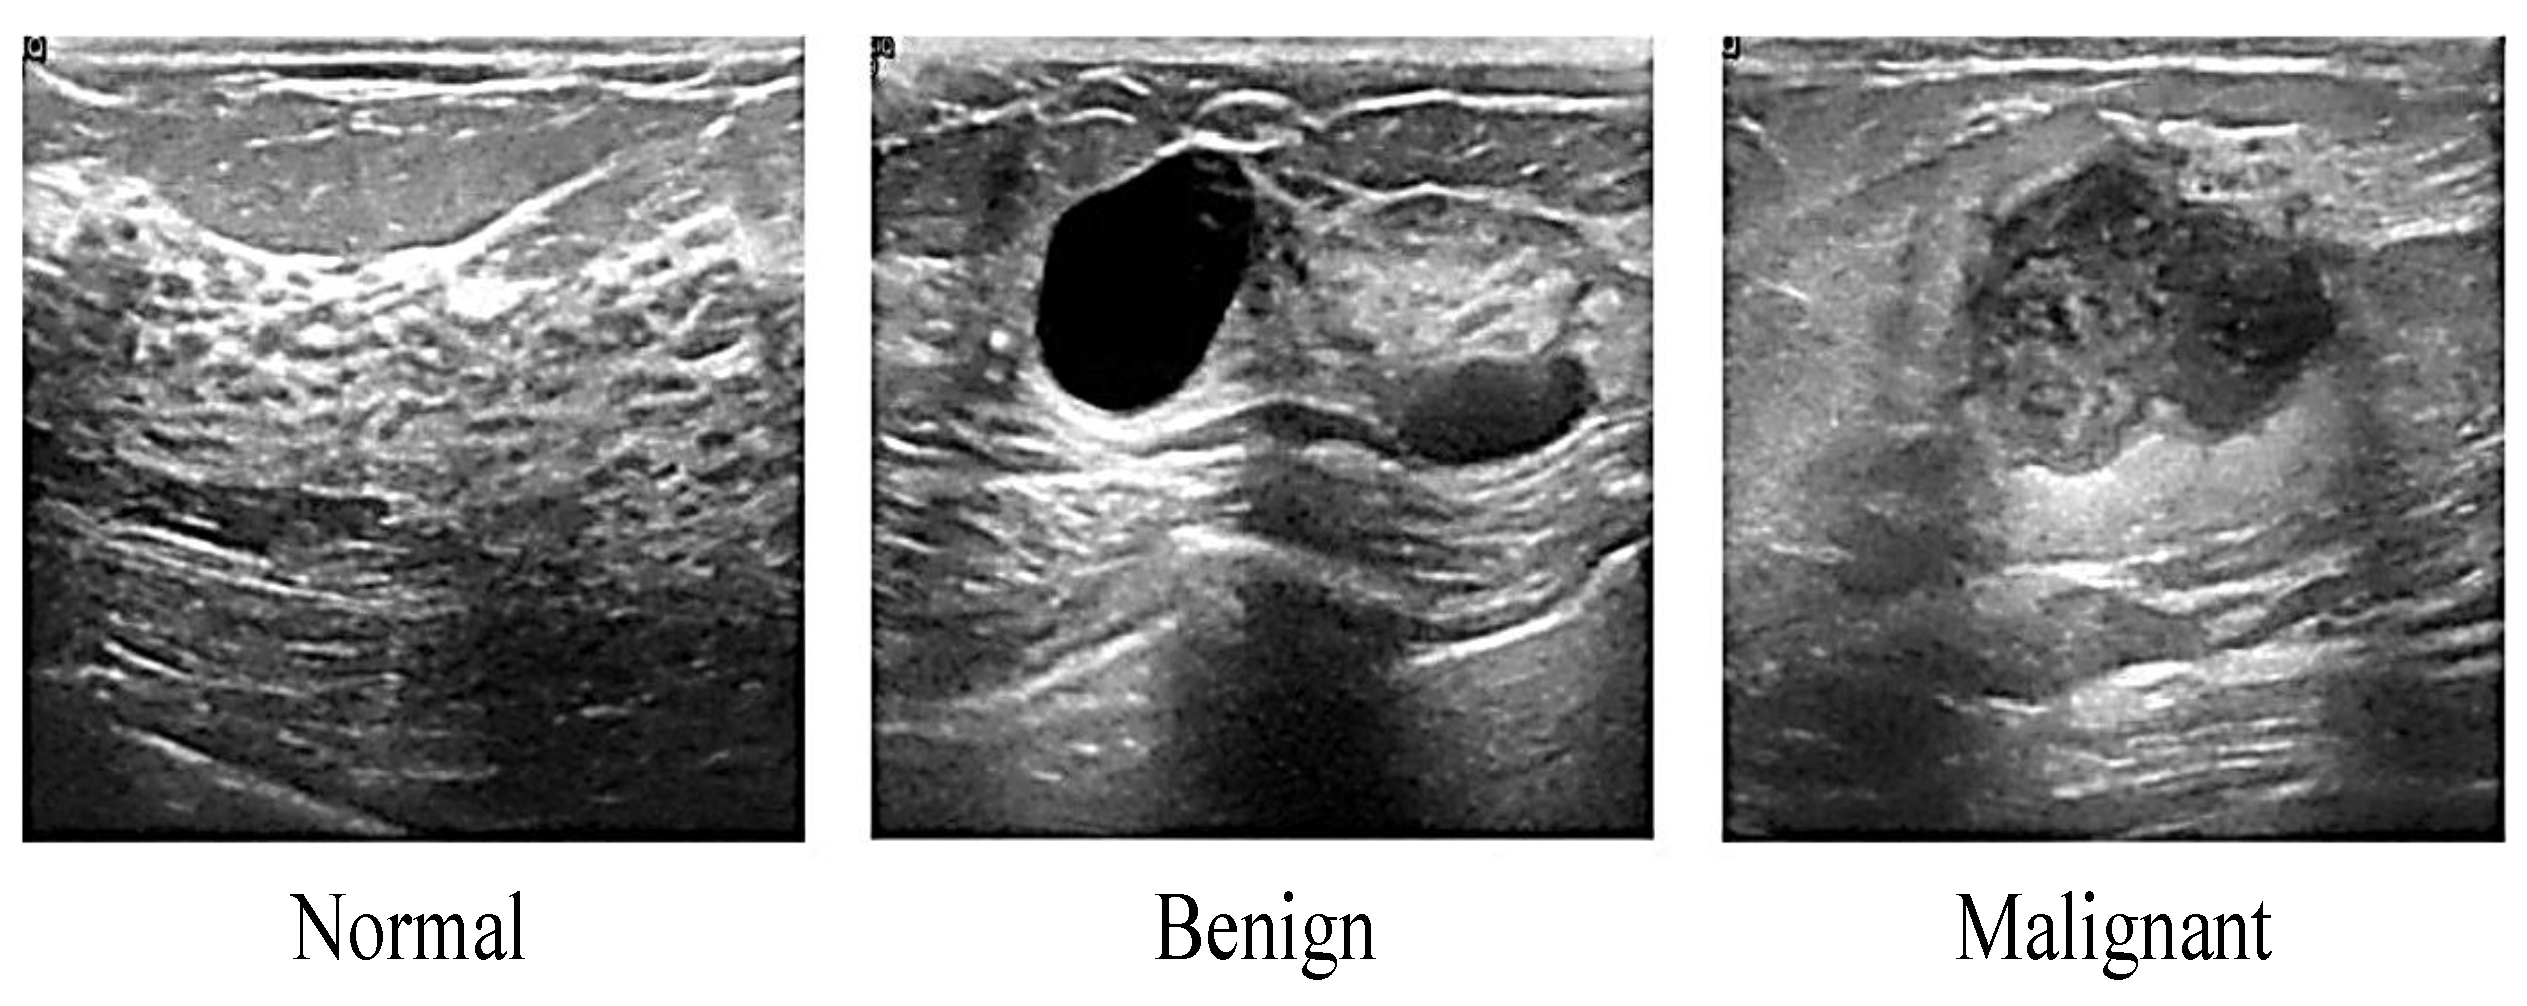

Ultrasound imaging (sonogram) is a medical tool that uses a high frequency of sound waves (echoes) to obtain real-time images of the body’s internal structures or detect suspicious nodular formations without involving ionizing radiation compared to MRI and mammogram. Ultrasound is a low-cost and non-invasive procedure for patients. There are two significant functions of ultrasound which are for diagnostic of internal body and pregnancy. The frequency range commonly employed in medical ultrasound is 2 to 18 megahertz, hundreds of times above the human hearing range [34,35,36]. A transducer is a device that rubs the patient’s skin across the area being investigated during an ultrasound. Although ultrasound is often used to prevent an invasive measure for diagnosis, sometimes it may overlook detecting the smaller size of masses that will carry false-positive and false-negative results. Ultrasound is suitable for women below 45 years and women with dense breasts, while mammography has progressive sensitivity in women 60 years and above [37]. The samples of ultrasound breast images are illustrated in Figure 4 and categorized into three classes, which are normal, benign, and malignant.

Figure 4.

Samples of Ultrasound breast image [38].